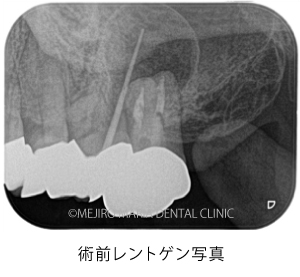

本症例の患者様は、左上7番(第2大臼歯)の歯ぐきから膿が出ており、来院されました。口腔内を確認すると根尖性歯周炎(※1)が原因で、左上7番根尖部(歯の根の先)に、瘻孔(フィステル・サイナストラクト ※2)が確認できました。CTにて膿が出ている箇所(写真の赤矢印)を確認すると、左上7番の根尖部に大きく広がっている病変(写真の赤丸)へ繋がっていることが分かりました。

当院で精密根管治療を施しましたが、瘻孔(フィステル・サイナストラクト)を消失させることが難しく、追加処置として歯根端切除術(今回は意図的再植術)を行いました。また、術前に撮影したCT画像より、根尖性歯周炎が原因と考えられる上顎洞炎(蓄膿症/ちくのうしょう)の併発も確認できました。